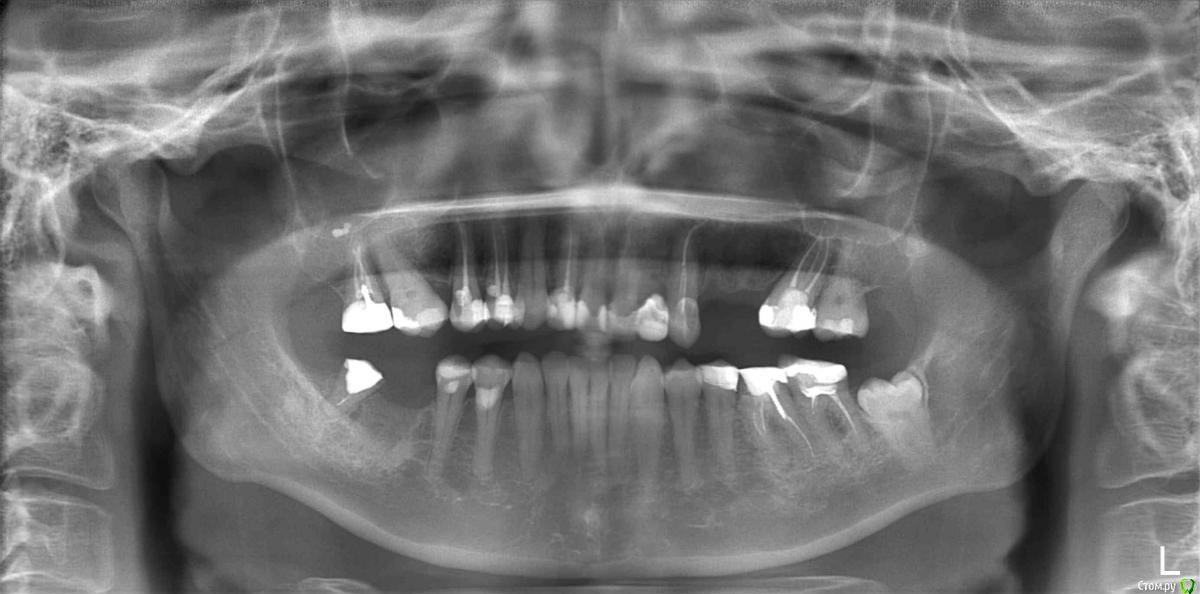

ElenaP. Опубликовано 17 августа, 2018 Поделиться Опубликовано 17 августа, 2018 Уважаемые доктора и специалисты! Помогите, пожалуйста, разобраться, что произошло с моими верхними зубами после установки цельного моста из 8 зубов. 1. Почему ширина всего зубного ряда уменьшилась на почти на 1,5 см, снимок "после" был сделан на той же машине, что и "до". 2. Почему провисло "небо" слева, что это означает? 3. Что за треугольники на снимке "после" в уголках верхней челюсти, похожие на разрез челюсти? Простите, если мои вопросы непрофессиональные, мой доктор считает, что все хорошо, хотя мост пришлось снять из-за сильнейших болей в лице и во рту, разумеется. Прошло более 5 месяцев, до сих пор хожу с временными мостами, но все страшно болит. Спасибо большое. На всякий случай даю снимок оригинальный, до того, как решилась на это безумие. Ссылка на комментарий